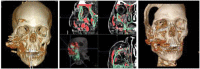

Zygomaticomaxillary (ZMC) fractures are the second most common facial fractures after nasal bone fractures. The zygoma, with its location and multiple points of articulations, lends itself to both facial structure and esthetics. Secondary ZMC deformities are complications of inadequate primary correction, delayed repair, or lack of repair. Secondary revisions of ZMC aim to correct ZMC displacement and projection and to address orbital discrepancies. Extensive correction involving significant orbital and malar defects requires zygomatic repositioning osteotomies and would greatly benefit from the utilization of virtual surgical planning, intraoperative navigation, and imaging. Minor corrections in malar projection can be corrected by onlay grafting and soft tissue augmentation and resuspension. Isolated or minor orbital corrections can be managed by autogenous or alloplastic material to restore lost orbital volume and anatomy.